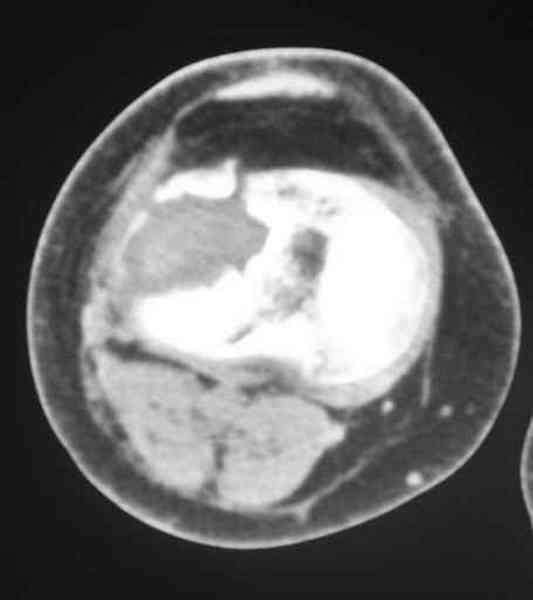

Есть ли возможность сделать КТ?

К большому сожалению КТ пока на ремонте, как запустять, сразу сделаю. Спасибо.

Я согласен с мнением доктора Соломина, что необходимо выполнить СТ. Это поможет Вам не только определить степень повреждения твёрдых тканей, но и увадеть степень сращения. Без СТ не возможно планировать дальнейшую тактику лечения.

У пациента основной проблемой является импрессионый перелом наружного мыщелка, уже неправильно сросшийся, по-видимому. Аппаратом закрыто можно только подправить угол на уровне метадиафиза. Что

улучшит разве что внешний вид конечности, но не решит основной проблемы - грубой деформации суставной поверхности.